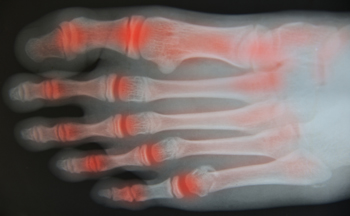

Rheumatoid Arthritis (RA) is an autoimmune disorder in which the body’s own immune system attacks the membranes surrounding the joints. Inflammation of the lining and eventually the destruction of the joint’s cartilage and bone occur, causing severe pain and immobility.

Although RA usually attacks multiple bones and joints throughout the entire body, almost 90 percent of cases result in pain in the foot or ankle area.